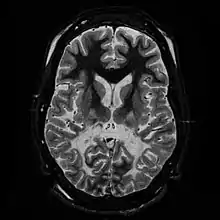

Les leucodystrophies sont des maladies rares caractérisées par un processus de changement démyélinisation du système nerveux central et périphérique, d'apparence primitive et non inflammatoire et aboutissant à une sclérose cérébrale. Ce sont presque exclusivement des maladies génétiques.

Le terme de leucodystrophie se rapporte à un groupe de maladies d'origine génétique affectant la myéline du système nerveux central. La myéline constitue la substance blanche du cerveau et de la moelle épinière. Elle enveloppe la fibre nerveuse de la même manière que l'isolant plastique d'un câble électrique : c'est elle qui permet la bonne conduction des messages nerveux. Dans les leucodystrophies, cette myéline peut avoir des problèmes pour se former ou pour se maintenir (parfois, on remarque une démyélinisation).